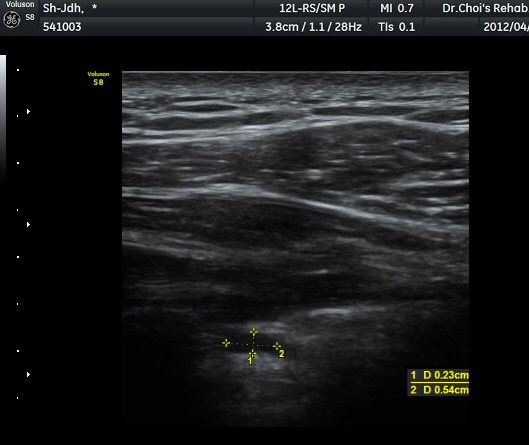

¾î±ú µÚ °üÀý¼ø °Ë»ç¿¡¼­ °üÀý¼ø Ç¥Ãþ¿¡ Àú¿¡ÄÚ ¼ö¾×Àú·ù°¡ °üÂûµÊ(»çÁø 4).

ŽÃËÀÚ¸¦ Á» ´õ µÚ·Î À̵¿ÇÏÀÚ °üÀý¼ø ³»Ãø °¡½Ã°üÀý¿À¸ñÆÐÀÓ(spinoglenoid notch)¿¡

¿øÇü¸ð¾çÀÇ Àú¿¡ÄÚ ³¶Á¾ÀÌ °üÂûµÊ(»çÁø 5, 6).